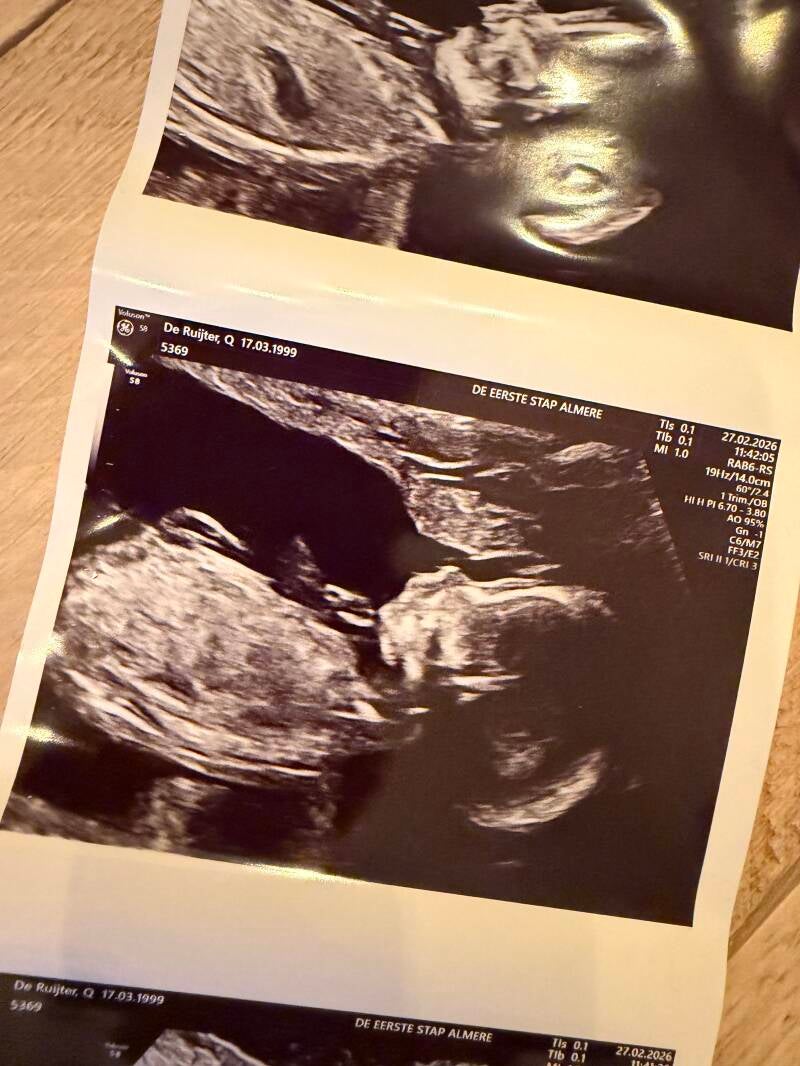

Ik ben weer zwanger en we zijn inmiddels al een paar echo’s verder. Bij de pretecho met 14 weken kon ik mijn nieuwsgierigheid niet langer tegenhouden. Ik wilde zo graag weten of jij een broertje of een zusje zou krijgen.

Het lijkt erop dat er een klein zusje voor je groeit. Een meisje… net als jij. Dat idee alleen al voelt zo bijzonder. Toch wil ik het binnenkort nog even zeker weten bij de gynaecoloog. Misschien omdat ik het zo graag goed wil hebben, misschien ook omdat ik het spannend vind om er echt op te vertrouwen.